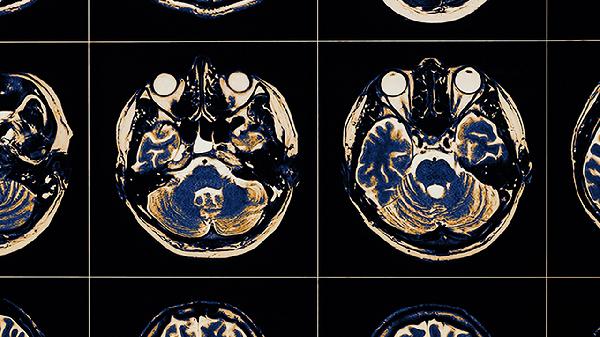

脑血栓会怎样呢?

脑血栓可能导致肢体麻木、言语障碍、意识模糊等症状。脑血栓通常由动脉粥样硬化、高血压、房颤等因素引起,可通过溶栓治疗、抗凝治疗、康复训练等方式干预。